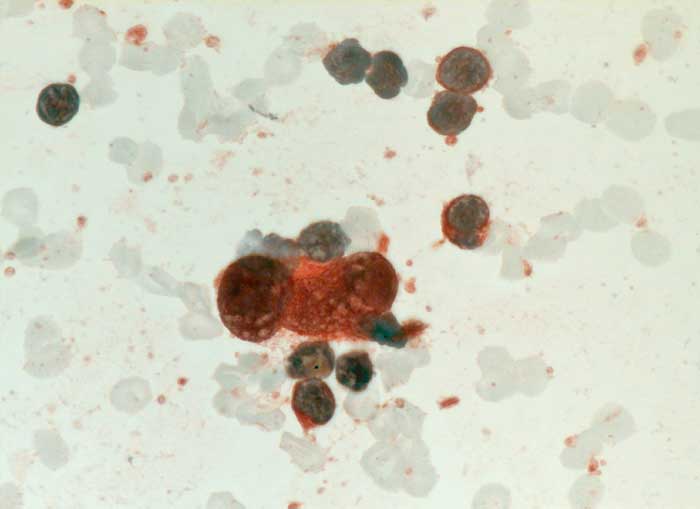

PathoPic – image database / PathoPic ID 6534 - Hodgkin Lymphom: Reed-Sternberg Zelle

Hodgkin Lymphom: Reed-Sternberg Zelle

Feinnadelpunktion Lymphknoten cervikal links: Die grosse zweikernige Reed-Sternberg Zelle ist positiv für CD30.

Histologisch Hodgkin Lymphom, Mischzelltyp.

Zytologische Diagnose: Malignes Hodgkin-Lymphom.

Befund spricht am ehesten für ein klassisches Hodgkin-Lymphom vom Mischtyp. Die genaue histologische Klassifikation sollte jedoch am histologischen Präparat erfolgen.

Immunhistochemie

CD30 (Ki-1)

630